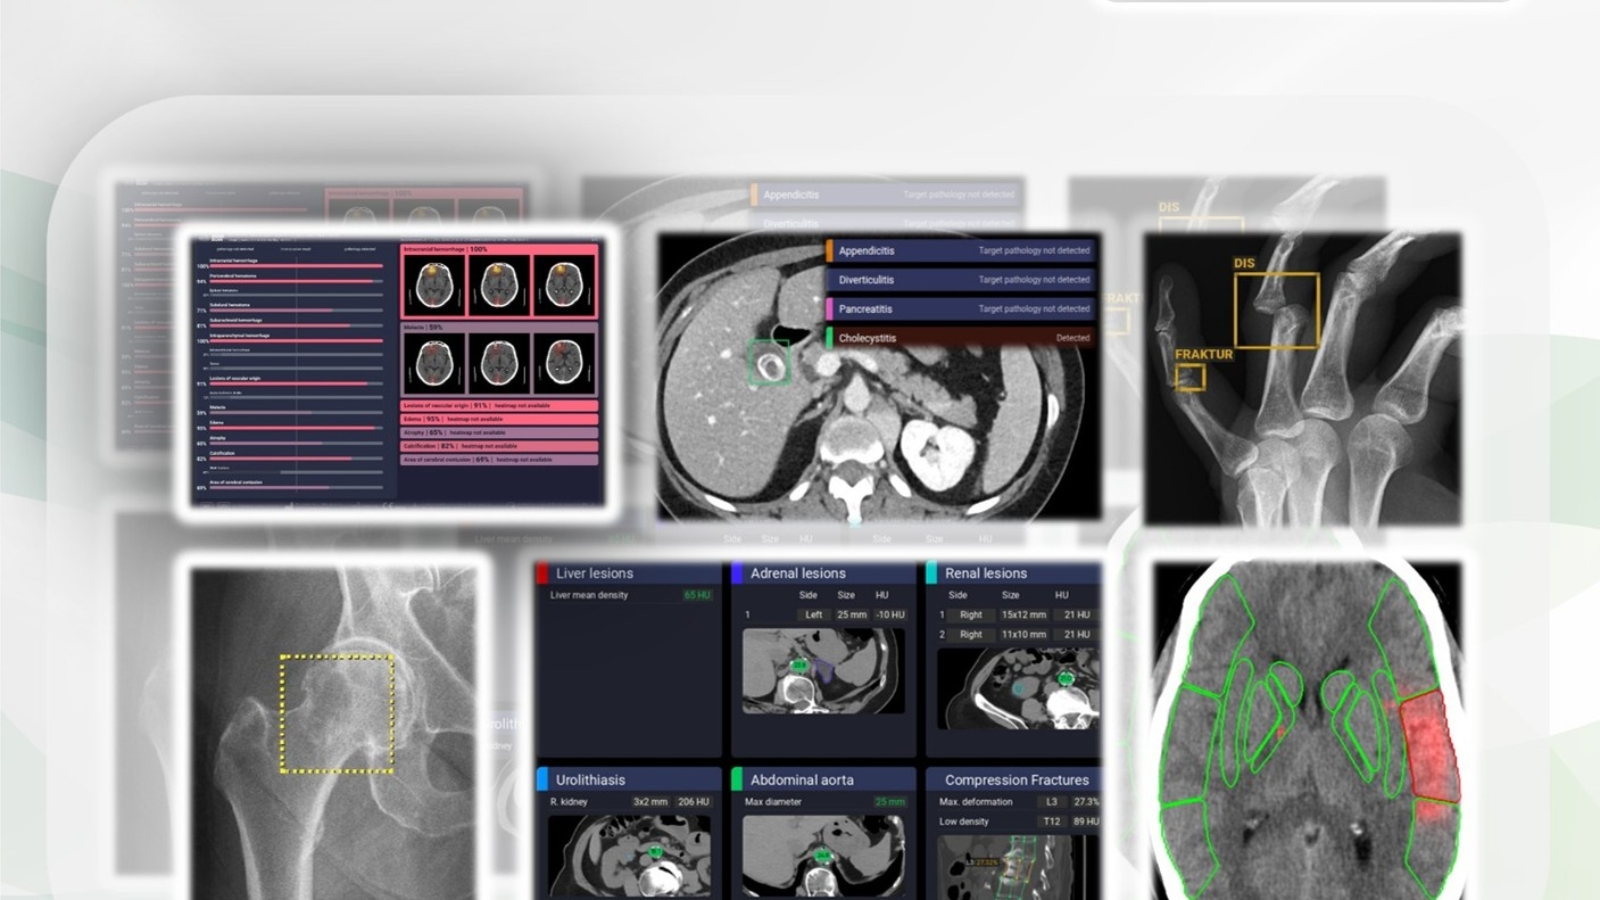

Im Jahr 2025 wurden 200 Patienten (Alter: 18 bis 8 Jahre, Mittelwert: 55 Jahre, Standardabweichung: ± 15 Jahre), die mit dem Verdacht auf eine akute Erkrankung der Bauchorgane zur CT des Abdomen an ERS Emergency Radiology Schueller, einem Anbieter teleradiologischer Dienste überwiesen worden waren, über zehn aufeinanderfolgende Wochen randomisiert und prospektiv in die Studie aufgenommen. Die CT-Untersuchungen dieser Patienten wurden mit dem AI-Assistenten xAID (Dover, DE, USA) ausgewertet. Der AI-Assistent bot Beurteilungen für die akute Cholecystitis, akute Pankreatitis, akute Appendizitis und die akute Divertikulitis. Die Radiologen beurteilten die CT-Untersuchungen, ohne die AI-Ergebnisse im Vorfeld zu kennen, und verglichen die radiologischen Befunde in einem zweiten Schritt mit den AI-Ergebnissen. Als Goldstandard galten die radiologischen Befunde sowie das bildgebende und klinische Follow up. Bei Diskrepanzen zwischen den radiologischen Befunden und den AI-Ergebnissen wurden die CT-Untersuchungen spätestens innerhalb von 30 Minuten einer Zweitbefundung unterzogen.

Von 200 Patienten konnten 54 AI-Ergebnisse nicht abgerufen werden. Für 146 Patienten diagnostizierten Radiologen und das klinische Follow 31 Patienten mit akuter Cholezystitis (21 %), 30 mit akuter Pankreatitis (20 %), 25 mit akuter Appendizitis (17 %) und 15 mit akuter Divertikulitis (10 %). Die Ergebnisse des AI-Assistenten sind für akute Cholezystitis in Tabelle A, für akute Pankreatitis in Tabelle B, für akute Appendizitis in Tabelle C und für akute Divertikulitis in Tabelle D aufgeführt; richtig positive (TP), falsch positive (FP), falsch negative (FN) und richtig negative (TN) Ergebnisse in absoluten Zahlen; Sensitivität, Spezifität, positiver Vorhersagewert (PPV) und negativer Vorhersagewert (NPV) in Prozent.

Bei der akuten Cholezystitis wurde ein FP bei einem chirurgisch und histologisch bestätigten, ausgeprägten Hydrops und einer Verdickung der Gallenblasenwand beobachtet.

Bei der akuten Pankreatitis wurde ein FP ohne jegliche positive CT-Zeichen beobachtet. Zwei FN traten bei Patienten mit den CT-Zeichen einer beginnenden akuten Pankreatitis auf.

Bei der akuten Appendizitis wurde ein FP in einem radiologisch und klinisch unauffälligen Patienten festgestellt. Die beiden FN wurden bei einem Patienten mit eindeutig positiven CT-Befunden und klinischen Symptome beobachtet.

Bei der akuten Divertikulitis traten zwei FP aufgrund einer Fehlinterpretation einer reaktiven Mesenteritis bei akuter Cholezystitis auf. Ein FN trat bei einem Patienten mit schwerer Pancolitis (entzündliche Darmerkrankung) auf, die sich klinisch, pathologisch, histologisch und radiologisch deutlich von einer Divertikulitis unterschied. Alle vier FN betrafen das linksseitige Colon.

Tabelle E zeigt das Gesamtergebnis des AI-Assistenten für alle akuten Pathologien.

Unseres Wissens ist unsere Studie die erste, die abdominale CT und AI im Kontext akuter Erkrankungen der Bauchorgane untersucht. Im Vergleich zu Ärzten verfolgen AI-Entwickler tendenziell einen pragmatischeren Ansatz bei der Mustererkennung, Segmentierung und Beschreibung von Bauchorganen. Dieser AI-Assistent unterteilt die Bauchhöhle primär anhand von vier Hauptkriterien. Während sich solche Algorithmen zur Berechnung einzelner Parameter, wie beispielsweise einzelner Organe, als geeignet erweisen können, wird der Mangel an menschlicher Sensibilität für das Gesamtbild, insbesondere beim akuten Abdomen, deutlich. Vor allem bei der akuten Cholezystitis und akuten Appendizitis verschlechtern sich die Ergebnisse, wenn der AI-Assistent auf Therapieoptionen stratifiziert werden soll. Bei der akuten Appendizitis können die Gründe auch in der oft ungewöhnlichen Lage der Appendix liegen, insbesondere bei komplizierten abdominalen Fällen, was der häufigsten Situation in der Teleradiologie entspricht. Wichtig zu beachten ist, dass ein AI-Assistent nicht in der Lage ist, den Verlauf eines akuten Abdomen abzubilden, da sich die CT-Muster von einer lokalen Entzündung über eine regionale Phlegmone bis hin zu einer diffusen Peritonitis und Perforation verändern können.